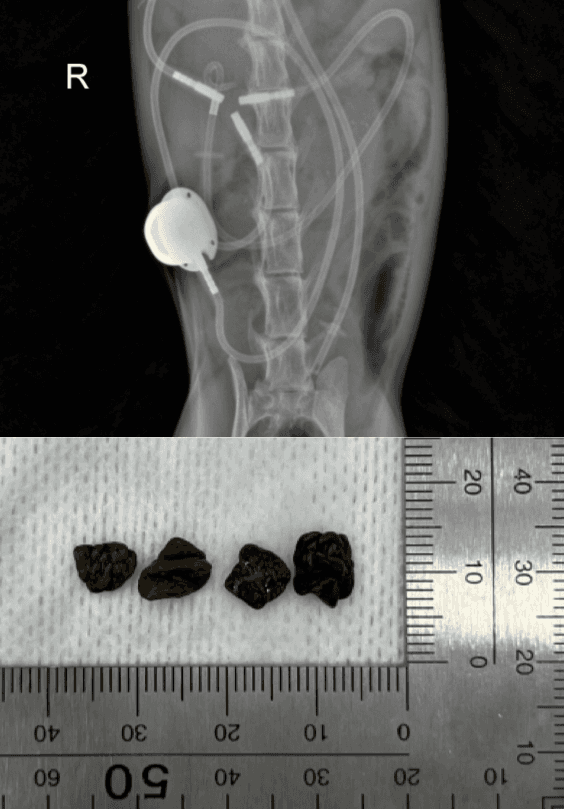

Urolithiasis Clinic

신장, 요관, 방광 결석에 대해 식이 조절을 통한 관리부터 필요한 경우 첨단 수술/시술까지 지원합니다. (성분 분석, 세척, 인공 요관 우회술)